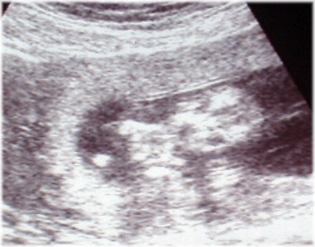

2003. május.29. (14. hét) Az első ultrahang felvétel